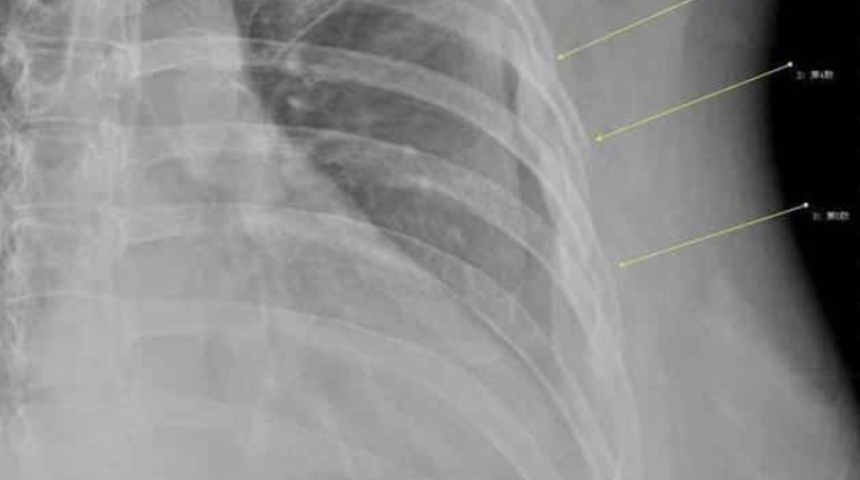

Doktor, ağrının nedenini bulmak için röntgen istedi ve asıl sorunu orada gördü. Han'ın üçüncü, dördüncü ve beşinci kaburgalarının şiddetli öksürük nedeniyle kırıldığını gördü. 7 yıldan uzun süredir su gibi kahve içen Han'a doktor teşhisi koydu; kemiklerinin eski sağlığını kaybetmesinin tek nedini aşırı kahve tüketimiydi. Doktor, 30 yaşındaki Han'a kemik yapısının 60 yaşındaki bir kadına eşdeğer olduğunu söyledi. Ve Han ne yazık ki erken osteoporoz yolundaydı.